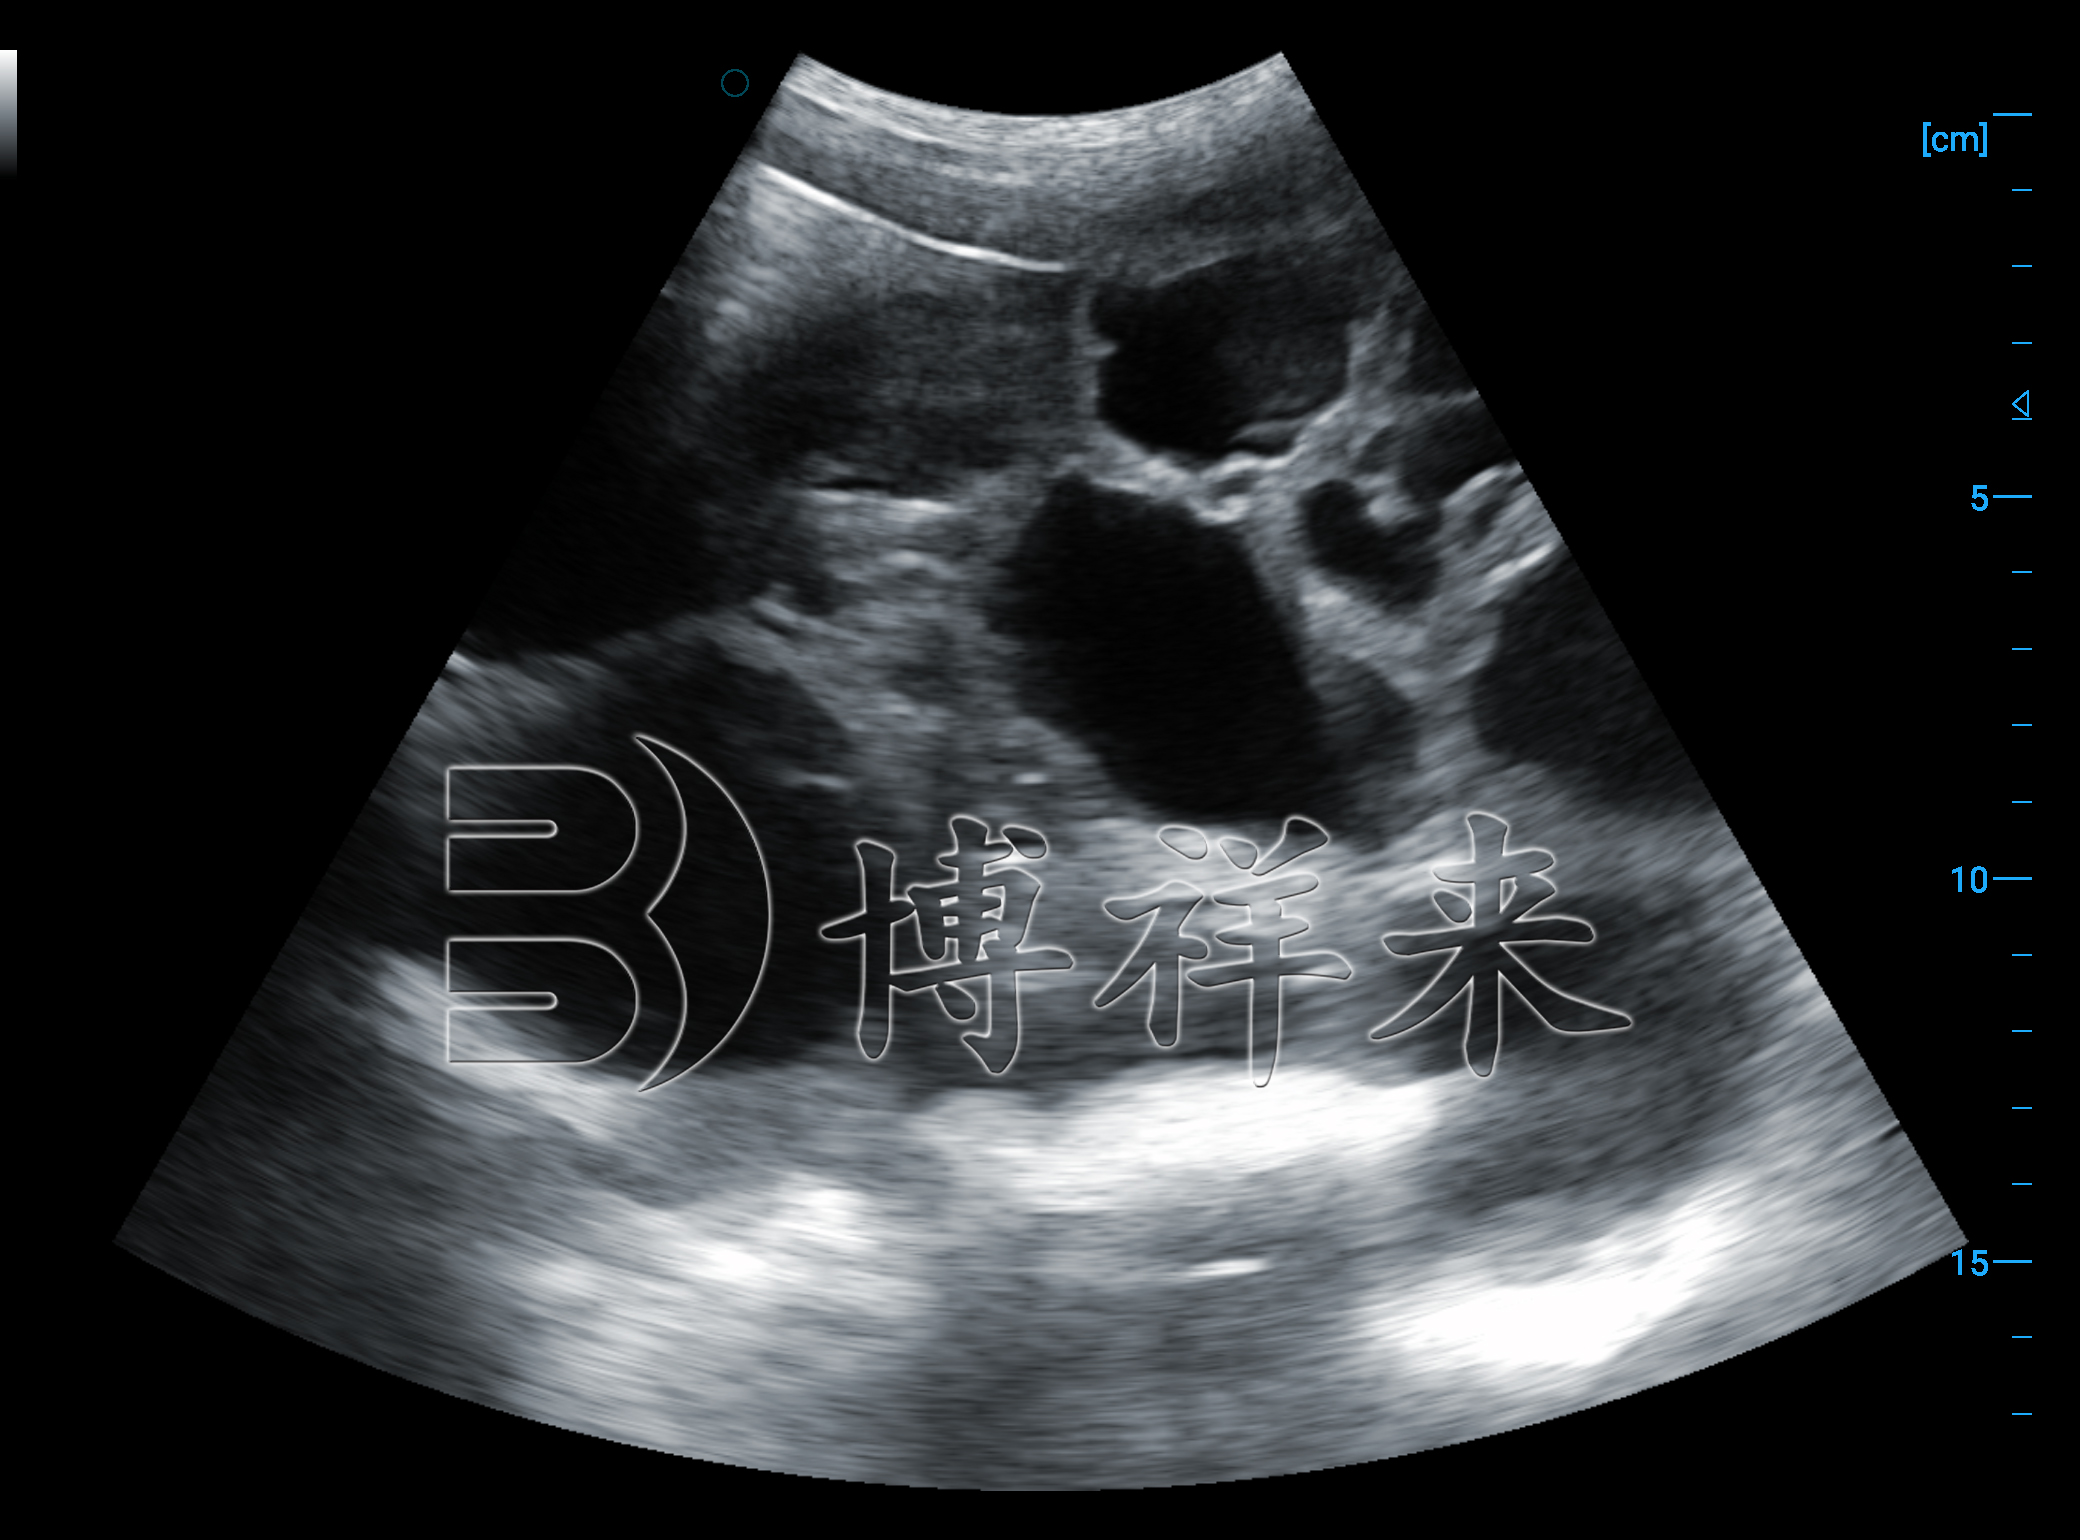

兽用B超仪通过超声成像来呈现子宫内部结构,而图像质量直接影响判断结果。如果探头选择不合适、参数设置不合理,或者操作过程中探头接触不良,都会导致图像对比度下降,细节不清晰。

在这种情况下,即使兽用B超仪具备检测能力,实际呈现出来的图像信息也可能不足以支撑准确判断。久而久之,就容易出现同一头动物不同时间检测结果不一致的情况。

因此,在动物测孕过程中,图像是否清晰,往往比“是否尽早检测”更重要。

在兽用B超仪的超声图像中,一些正常的生理结构或暂时性变化,与早期妊娠特征在视觉上存在一定相似性。如果操作者对动物生殖解剖结构不够熟悉,就容易产生误判。

例如,将非妊娠状态下的子宫内容物变化误认为妊娠迹象,或者在判断过程中只关注单一画面,而忽略连续观察和整体对比。这类误判,在初次使用兽用B超仪进行动物测孕时尤为常见。